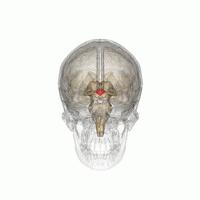

Hypothalamic nuclei on one side of the hypothalamus, shown in a 3-D computer reconstruction[12]